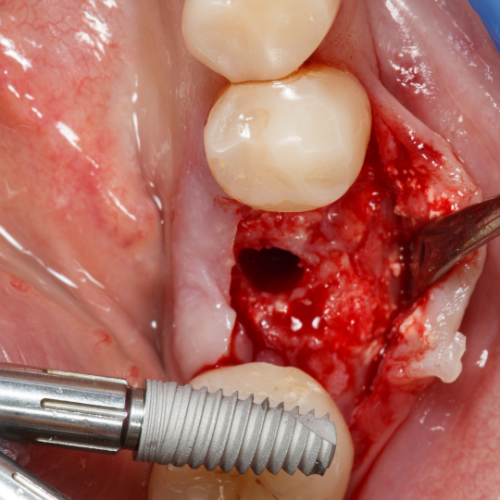

Removal of Impacted Third Molars

Our experienced dental surgeons have removed 1000s of impacted third molars

Dental Implants

From immediate implants to full arch all-on-x solutions, our team of clinicians have the experience to deliver great results for your patients.

Our experienced dental surgeons will bring everything they need to ensure excellent and safe IV sedation and dental surgery for your patients in the comfort of your office.